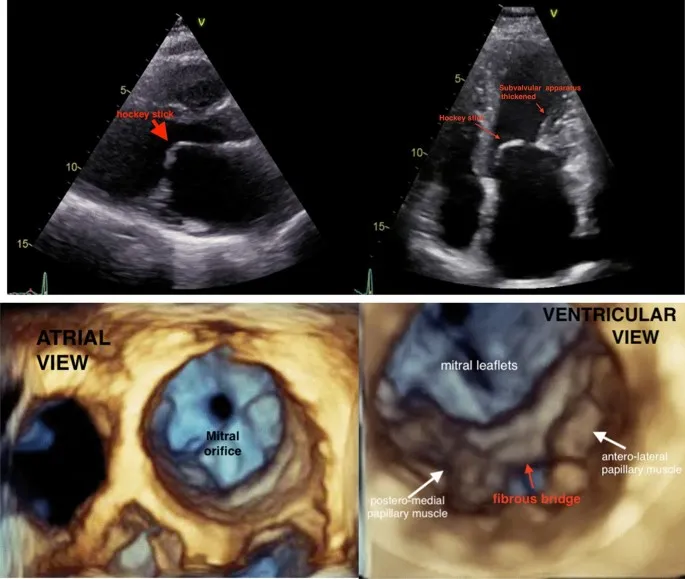

Mitral Stenosis - The Atrial Jam

- Etiology: Almost exclusively rheumatic heart disease.

- Pathophysiology: Obstruction at the mitral valve → ↑ LA pressure → LA enlargement → pulmonary hypertension → right-sided HF.

- Murmur: Opening snap (OS) followed by a low-pitched mid-diastolic rumble, best heard at the apex.

- Complications: Atrial fibrillation (from LA stretch), hoarseness (Ortner's syndrome), dysphagia.

⭐ The interval between S2 and the opening snap is inversely proportional to the severity of the stenosis; a shorter S2-OS interval means more severe MS.